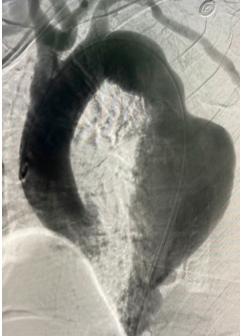

Dilatación segmentaria significativa de un trayecto vascular ( arterial o venoso) con riesgos de roptura y puede provocar la muerte.